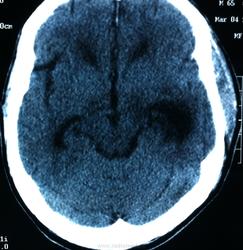

КТ контроль после операции.

Мне видится так. Иначе в данной локализации просто неоткуда расти оболочечной опухоли. На контрольной КТ, после декомпрессии, когда срединные структуры стали действительно срединны, правое обызвествленное сосудистое сплетение видно отчетливо, а левое, где оно? Ведь если бы образование компремировало, то после операции, когда часть мозга пролабировало в трепанационное отверстие мы бы увидели и левое сосудистое сплетение, но оно интимно связано с образованием и даже "потянулось" за ним в сторону декомпрессионного отверстия, потому что это и есть "росток" откуда выросла опухоль.